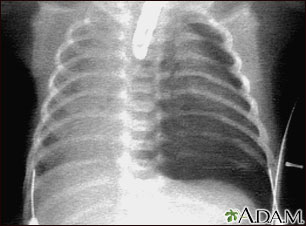

Pneumothorax occurs when air leaks from inside of the lung to the space between the lung and the chest wall. The lung then collapses. The dark side of the chest (right side of the picture) is filled with air that is outside of the lung tissue.